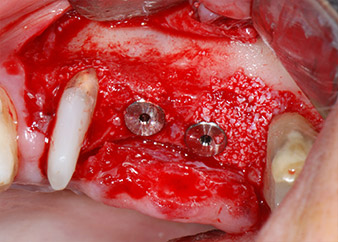

Implant beds were prepared at sites 25 and 26 with rotary instruments, used in a contra-angle handpiece with a 20 : 1 transmission ratio with an updated powerful implant motor (Implantmed, W&H) (Fig. 8).

Prior to implant placement, and following verification of an intact Schneiderian membrane (Fig. 9), the internal sinus floor was augmented at both implant sites by means of xenogeneic bone substitute material (Bio-Oss, Geistlich Biomaterials) (Fig. 10).

The implants (Restore, Keystone Dental, diameter 3,75 mm, length 8.0 mm) were placed with the implant motor

(Figs. 11 and 12).